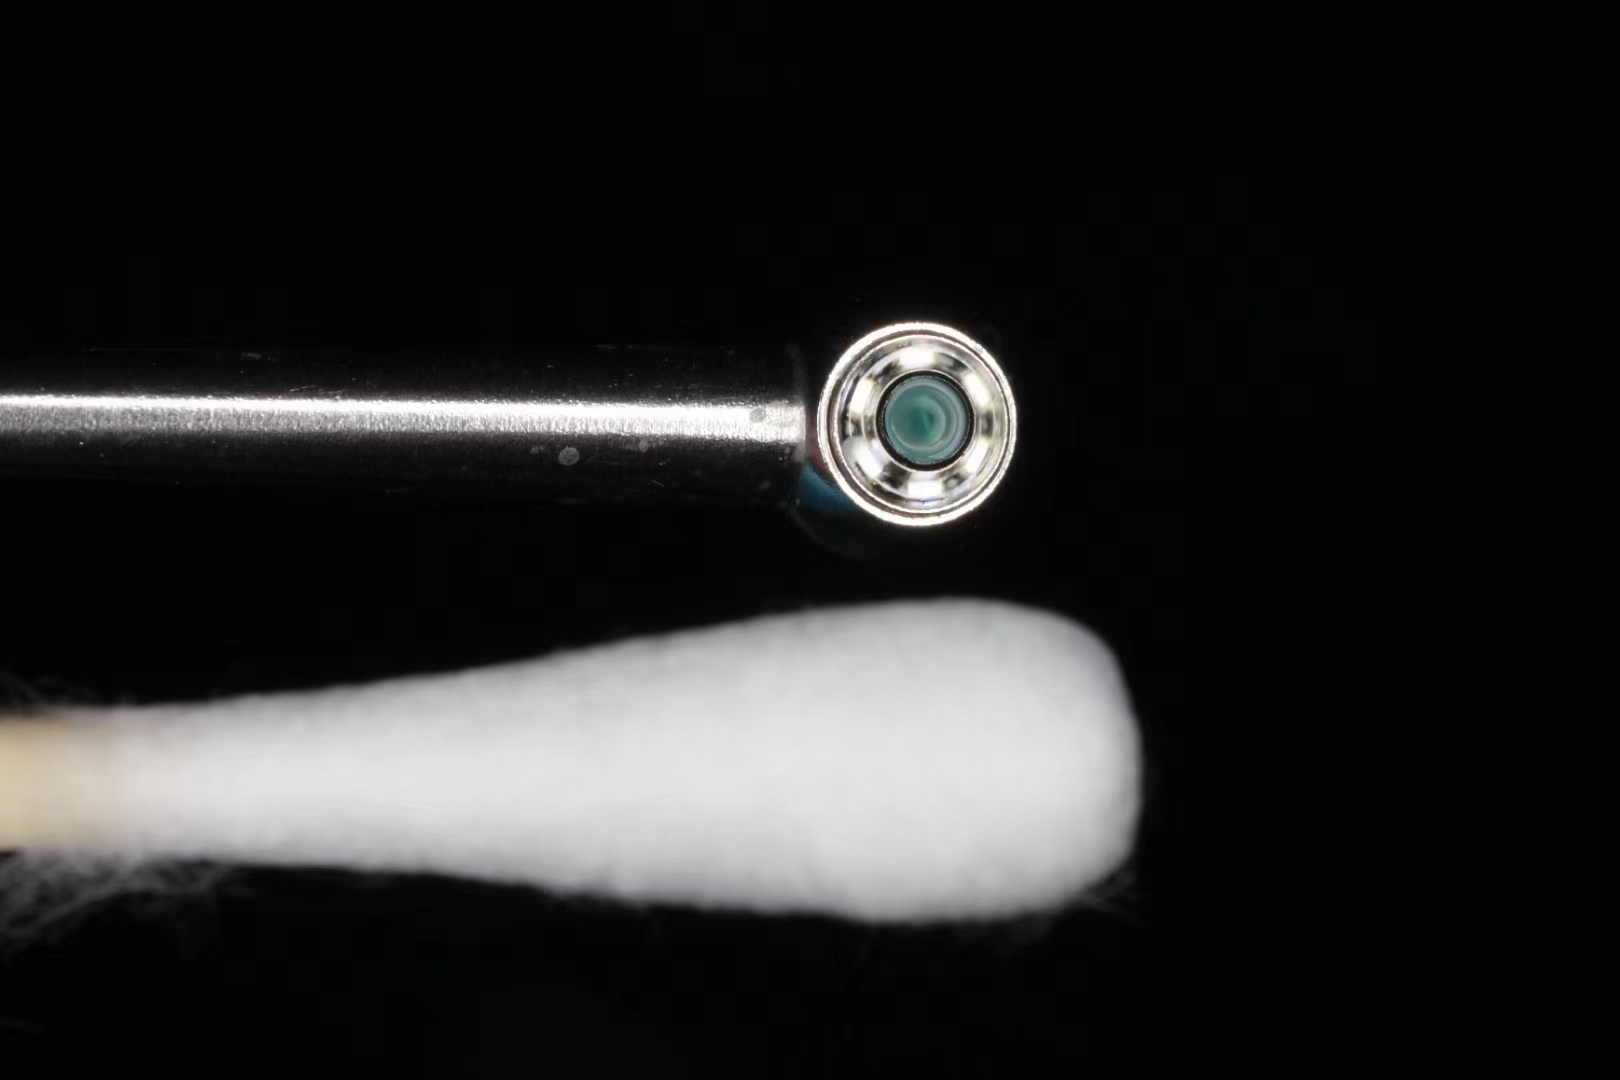

* Image sensor: HD 1/9 image sensor chip, clearer image